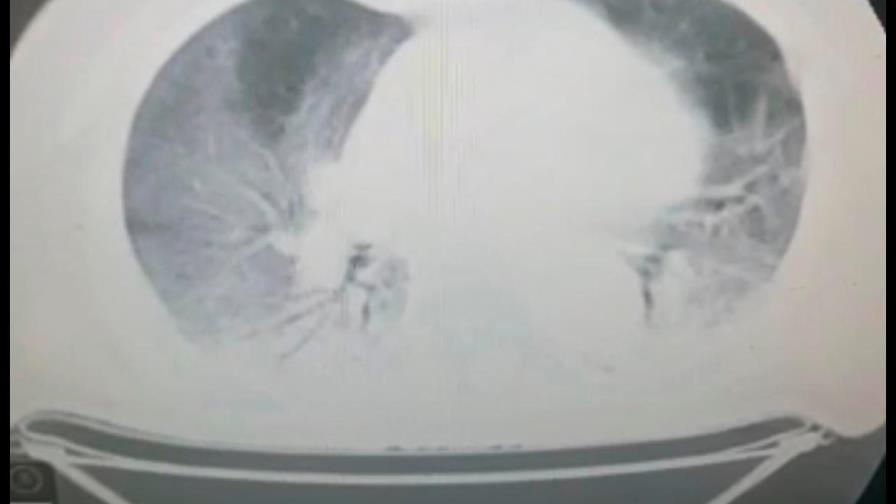

La afirmación la realiza el ministro de Salud Pública, Daniel Rivera, en declaraciones a Diario Libre, al señalar a través de unas radiografías del tórax, que los no vacunados llegan a los centros hospitalarios con los pulmones altamente comprometidos.

Entre tanto, la presidenta de la Sociedad de Neumología y Cirugía del Tórax, Evangelina Soler, explicó que los pacientes que se infectan de COVID-19 tienen un curso de la enfermedad muy diferente dependiendo de los factores de riesgo de cada persona; sin embargo, los que tienen las tres dosis se ven poco afectados.

Soler indicó que todo lo contrario ocurre en los pacientes no vacunados, los cuales presentan afecciones de moderadas a graves, según factores de riesgo.

“Pueden tener importantes daños al aparato respiratorio, con limitaciones a la actividad física y en muchos casos se produce una importante dependencia de oxígeno, lo que se traduce en mayor esfuerzo respiratorio”, indicó.

La especialista explicó que esta situación hace que los pacientes consuman mucha energía y se produzca pérdida de la fuerza muscular y se convierte en un círculo vicioso que conlleva a mayor deterioro de la funcionabilidad del pulmón.